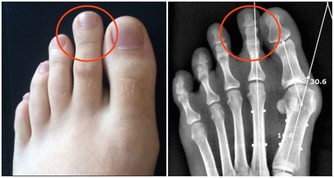

肥胖真的超燒錢!肥胖有可能是你花了很多錢吃喝,也有人會花很多錢來減肥,肥胖甚至會引起很多疾病,而且去治療這些疾病,健保還得給付;醫界更預估,到了2020年時,健保預算的1/3是用來給付因為肥胖所引起的疾病。 高血壓+高血脂+糖尿病+心血管疾病+癌症 有哪些疾病是因為肥胖所引起、會需要用到健保來看病的呢?天主教聖馬爾定醫院家庭醫學科主任陳志誠指出,肥胖會出現代謝症候群,進而引起高血壓、高血脂、糖尿病,並且也會造成心血管的問題,肥胖甚至會增加一些癌症的風險,例如大腸癌及乳癌,肥胖都是危險因子。 退化性關節炎+對磨疹+淋巴水腫+睡眠呼吸中止症 陳志誠主任進一步指出,肥胖還會使得膝關節和髖關節負擔大,以致出現退化性關節炎,皮膚也會因為容易在皺摺處引起對磨疹或是感染,增加淋巴性水腫的可能性,肥胖更可能產生睡眠呼吸中止症,影響睡眠品質。 成人過重及肥胖盛行率為38% 根據世界衛生組織研究報告顯示,全球有將近1/3成人、1/4孩童過重,總計目前全球肥胖或過重的人口超過21億。而根據衛福部所進行的2013年「國民營養健康狀況變遷調查」結果顯示,成人過重及肥胖盛行率為38%;也就是說,不到三個成年人中,就有一人過重或是肥胖;醫界並預估,到2020年時,將有1/3健保預算,會用來給付因為肥胖所引起的相關疾病診療費用。。 飲食與運動是減重不二法門 因此,減重除了能改善體態之外,更重要的是能預防諸多疾病,而飲食與運動則是減重的不二法門;陳志誠主任則是強調,減重要成功,其關鍵就是要先找到自己想改變的原因,而且慢慢的把不好的習慣一個一個改過來,不求速效,而是考慮可以維持多久! 健康醫療網: http://www.healthnews.com.tw/news/article/29601